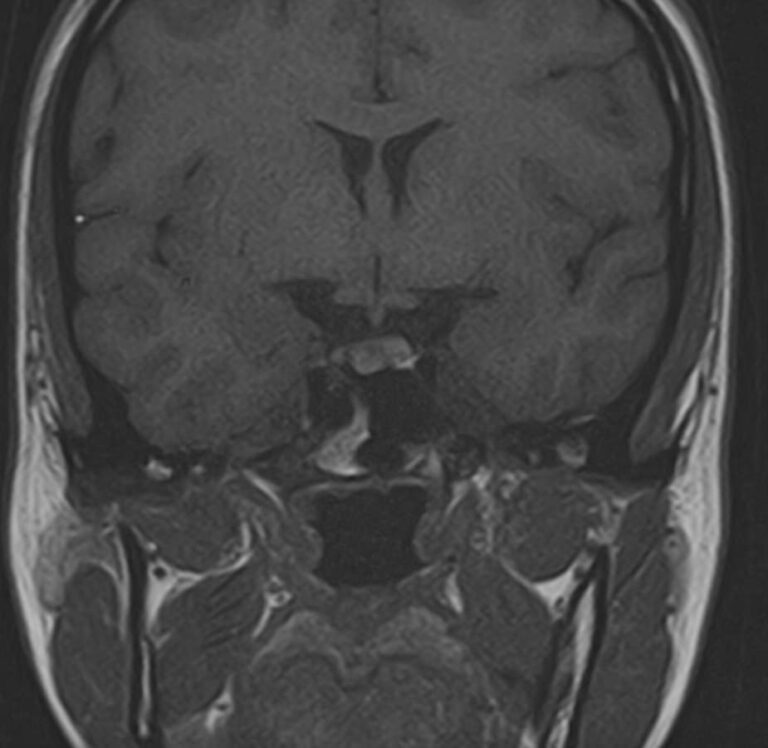

Поскольку гипофиз имеет очень маленькие размеры и расположен в глубине головы, досконально изучить его структуру можно только с помощью МРТ. Ни один другой из существующих методов визуализации не способен дать настолько четкие изображения и данные о состоянии гипофиза. Расшифровка результатов выполняется рентгенологом.

С помощью МРТ гипофиза можно создать его трехмерное изображение с высокой степенью детализации. Это позволяет обнаружить патологические изменения на самых ранних этапах, начиная от аномалий развития, сосудистых нарушений, воспалительных процессов и заканчивая опухолями разной природы.

МРТ гипофиза выполняется в нашей клинике выполняеется только с контрастным усилением, что повышает четкость получаемых изображений, а по особенностям распределения контрастного препарата в тканях можно с высокой точностью не только обнаружить доброкачественные и злокачественные опухоли, но и исследовать их локализацию, структуру, определить границы и заметить метастазы.

Чаще всего исследование проводится для диагностирования аденомы гипофиза и определения ее величины: микроаденомы (до 10 мм), макроаденомы (10—30 мм) и гигантской аденомы (более 30 мм). Также с его помощью обнаруживается неоднородностьструктуры, асимметрия границ, изменения положения воронки гипофиза и ее строения, а также деформации окружающих костных тканей.